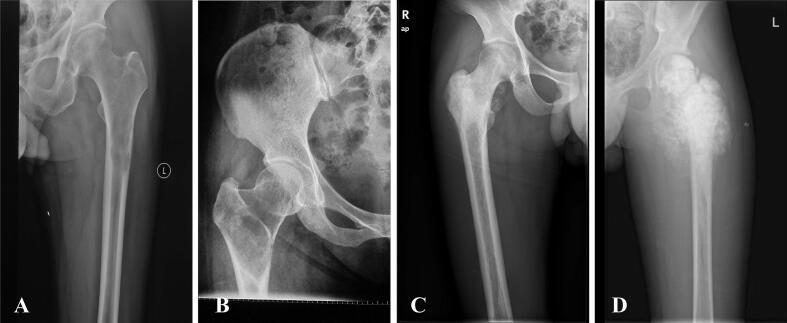

Of the 85 patients included, 27 cases underwent unplanned surgery at external hospitals, including 16 males and 11 females, with a median age of 44 years (range: 11-81 years). Initial preoperative radiologic findings in these patients undergoing unplanned surgery showed no periosteal reaction or soft tissue mass. No significant differences in OS, EFS, or LRR were observed between the unplanned and planned surgery groups (p > 0.05). However, MSTS scores were significantly lower in the unplanned surgery group (p < 0.001).

纳入的85例患者中,27例在外部医院接受了非计划性手术,其中男性16例,女性11例,中位年龄44岁(范围:11-81岁)。这些接受非计划性手术的患者术前最初的影像学检查结果显示无骨膜反应或软组织肿块。非计划性手术组和计划性手术组在OS、EFS或LRR方面未观察到显著差异(p>0.05)。然而,非计划性手术组的MSTS评分显著更低(p<0.001)。